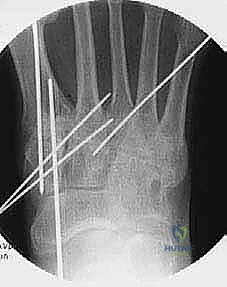

"We'll use Kirschner wires (K-wires) and guide pins for temporary stabilization."

-

First TMT Joint Temporary Fixation:

- "Let's make a small stab incision over the medial aspect of the medial cuneiform, just through the skin. Use a small hemostat to dissect down to bone, carefully retracting the tibialis anterior tendon."

- "Now, we'll place our first 0.062 Kirschner wire. Aim it from the dorsal-medial aspect of the medial cuneiform, angling distally and slightly plantar, into the plantar aspect of the first metatarsal base. This K-wire should be placed where one of our final screws will go."

- "Next, place a second 0.062 K-wire. This one goes from the dorsal aspect of the first metatarsal shaft, angling proximally and slightly plantar, into the plantar aspect of the medial cuneiform. These two crossed K-wires will hold the first TMT joint securely in its reduced position."

* "Once these are in, check your fluoroscopy. AP, lateral, and oblique views. Confirm good reduction and alignment of the first ray."

- Second TMT Joint Temporary Fixation:

- "Now, let's stabilize the second metatarsal. We'll use a guide pin from our 3.0-mm cannulated screw set for this. Make a small stab incision dorsally, protecting the tibialis anterior tendon."

- "Reduce the second metatarsal to the intermediate cuneiform and ensure it's aligned with the first metatarsal base. Again, palpate the metatarsal heads to confirm they are level and plantigrade."

- "Aim the guide pin from the base of the second metatarsal, angling proximally and slightly medially, into the intermediate cuneiform. This provides axial compression and alignment."

- Third TMT Joint Temporary Fixation:

- "Finally, for the third metatarsal, make a stab incision on the lateral forefoot. Insert another guide pin from the 3.0-mm cannulated screw set."

- "Reduce the third metatarsal to the lateral cuneiform, ensuring it's in a plantigrade position relative to the second metatarsal. Aim the guide pin from the base of the third metatarsal into the lateral cuneiform."

- Final Fluoroscopic Check:

- "Before we proceed to definitive fixation, let's get a full set of intraoperative fluoroscopy images: AP, lateral, and oblique. We need to ensure adequate reduction and opposition of all arthrodesis surfaces, and that our temporary wires are in good position. Look for any gapping or malalignment. Are all metatarsal heads level on the lateral view? Is the alignment restored on the AP?"